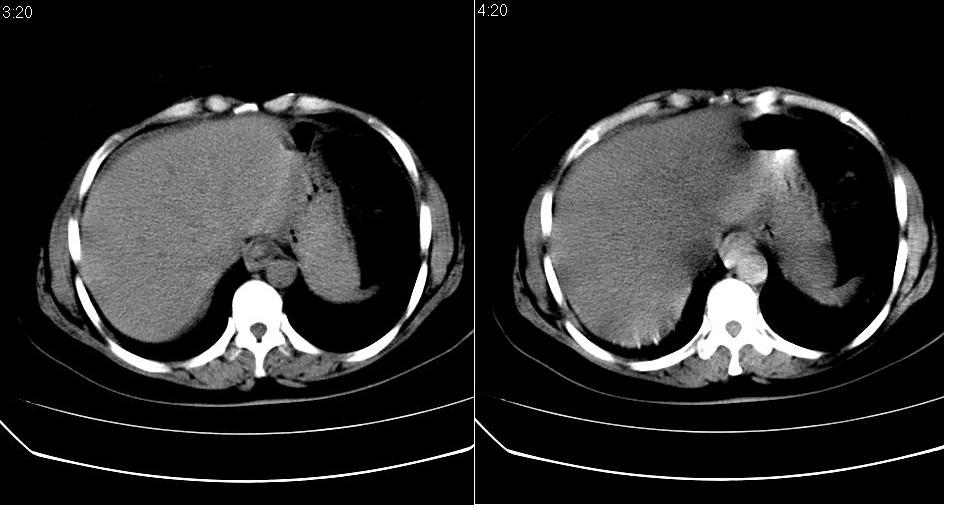

女 52岁,腹痛两天,无其它不适。

左肾周筋膜增厚,肾前间隙积液,胰腺肿大,胆囊结石,胰腺炎

胆囊结石 胰腺炎伴胰尾假性囊肿形成.

支持除胰腺假性囊肿外的一切诊断,胰腺低密度应该是坏死。

胰头部囊状影是十二指肠。左侧肾前筋膜增厚、少量积液,胰腺增大,边缘模糊,支持胰腺炎。

1、慢性胆囊炎,胆囊结石、胆总管结石。诊断依据:胆囊内、胆总管内见高密度影,胆囊已有萎缩,说明时间已较长,胆囊壁有增厚。

2、胆源性胰腺炎,诊断依据:同1外+左肾周筋膜增厚,肾前间隙积液,胰腺肿大。